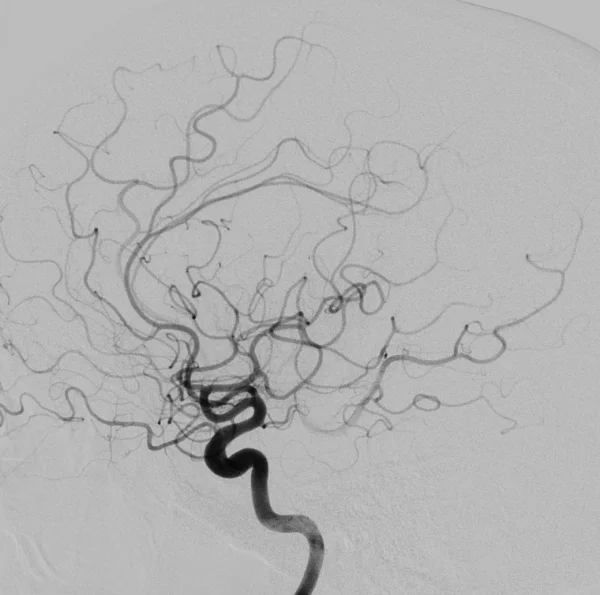

Cet examen invasif, réalisé sous anesthésie locale, permet d’obtenir une analyse morphologique et dynamique très précise des artères et des veines du cerveau ou de la moelle épinière en rendant les vaisseaux sanguins visibles aux rayons X en y injectant un produit de contraste à l’aide d’un tuyau (cathéter) que l’on navigue sous contrôle radiologique depuis le poignet ou le pli inguinal.

L’angiographie cérébrale est un examen diagnostic qui permet de visualiser les vaisseaux qui amènent le sang au cerveau (artères) et ceux qui le ramènent vers le coeur (veines). Les termes artériographie et phlébographie désignent respectivement l’étude spécifique des artères et des veines. Lorsque l’on s’intéresse aux vaisseaux de la moëlle épinière, on parle d’angiographie médullaire.

L’objectif est de rechercher une anomalie des vaisseaux pouvant expliquer vos symptômes. comme une malformation des vaisseaux (anévrysme, malformation artério-veineuse, fistule…), un rétrécissement ou l’occlusion totale d’une artère.

Afin d’éviter les infections, le médecin qui pratique l’examen porte une tenue “stérile”. L’équipe paramédicale désinfecte la peau à hauteur du pli de l’aine et/ou du poignet (le plus souvent à droite). On vous recouvre ensuite d’un champ stérile avec un ou des orifices permettant de travailler. Une anesthésie locale est pratiquée en regard de l’artère fémorale ou radiale et un petit tuyau (introducteur) y est placé. Cet accès permet ensuite de coulisser un second tuyau (cathéter) qui sera guidé par le médecin sous contrôle radiologique jusqu’aux artères que l’on souhaite étudier. Plusieurs séries d’images sont alors réalisées en injectant du produit de contraste iodé dans le flux sanguin à l’aide du cathéter et en faisant des radiographies dynamiques de de ce “moulage” des vaisseaux. A chaque injection, vous pouvez ressentir une sensation de chaleur dans la tête, une sensation de vertige, un goût métallique, des scintillements visuels. Ces symptômes durent quelques secondes et disparaissent ensuite complètement.